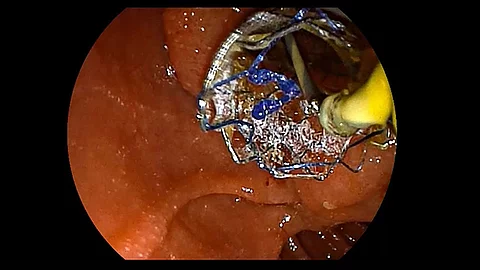

Endoskopisches LehrvideoStentwechsel mit Soehendra Stent-Retriever

Wie wechselt man einen Stent achsgerecht mit einem Soehendra Stent-Retriever? Die hierzu notwendigen Schritte zeigt Ihnen Prof. Dr. Jochen Weigt im Video. Zudem erläutert er, wann diese Technik angewendet wird.